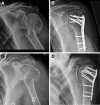

Material and methods: Patients were included undergoing ORIF by use of locking plates for displaced two-part surgical neck type proximal humeral fractures. Reduction and functional outcomes were compared between procedures that were conducted by trauma surgeons [TS], senior (>2 years after board certified) trauma surgeons [STS] and trauma surgeons performing ≥50 shoulder surgeries per year [SS]. Quality of reduction was measured on postoperative x-rays. Functional outcomes were assessed by gender- and age-related Constant Score (nCS). Secondary outcome measures were complication and revision rates.

Results: Between 2002-2014 (12.5 years) n = 278 two-part surgical neck type humeral fractures (AO 11-A2, 11-A3) were included. Open reduction and internal fixation was performed with the following educational levels: [TS](n = 68, 25.7%), [STS](n = 110, 41.5%) and [SS](n = 77, 29.1%). Functional outcome (nCS) increased with each higher level of experience and was significantly superior in [SS] (93.3) vs. [TS] (79.6; p = 0.01) vs. [STS] (83.0; p = 0.05). [SS] (7.8%) had significantly less complications compared with [TS] (11.3%; p = 0.003) and [STS](11.7%; p = 0.01) moreover significantly less revision rates (3.9%) vs. [TS](8.2%) and [STS](7.4%) (p<0.001). Primary revision was necessary in 13 cases (4.7%) due to malreduction of the fracture.

Conclusion: Quality of reduction and functional outcomes following open reduction and internal fixation of displaced two-part surgical neck fractures are related to the surgeon's experience. In addition, complications and revision rates are less frequent if surgery is conducted by a trauma surgeon performing ≥50 shoulder surgeries per year.